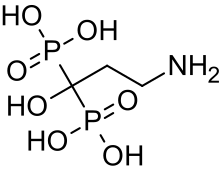

| Medication | Bisphosphonates[7] |

Although there is no cure,[10] most cases of OI do not have a major effect on life expectancy,[1]: 461 [15] death during childhood from it is rare,[10] and many adults with OI can achieve a significant degree of autonomy despite disability.[18] Maintaining a healthy lifestyle by exercising, eating a balanced diet sufficient in vitamin D and calcium, and avoiding smoking can help prevent fractures.[19] Genetic counseling may be sought by those with OI to prevent their children from inheriting the disorder from them.[1]: 101 Treatment may include acute care of broken bones, pain medication, physical therapy, mobility aids such as leg braces and wheelchairs,[10] vitamin D supplementation, and, especially in childhood, rodding surgery.[20] Rodding is an implantation of metal intramedullary rods along the long bones (such as the femur) in an attempt to strengthen them.[10] Medical research also supports the use of medications of the bisphosphonate class, such as pamidronate, to increase bone density.[21] Bisphosphonates are especially effective in children,[22] however it is unclear if they either increase quality of life or decrease the rate of fracture incidence.[7]

Bisphosphonates

In 1998, an initial observational trial demonstrated the effectiveness of intravenous pamidronate, a bisphosphonate which had previously been used in adults to treat osteoporosis. In severe OI, this trial showed that pamidronate reduced bone pain, prevented new vertebral fractures, reshaped previously fractured vertebral bodies, and reduced the number of long-bone fractures.[104]

Although oral bisphosphonates are more convenient and cheaper, they are not absorbed as well, and intravenous bisphosphonates are generally more effective, although this is under study. Some studies have found oral and intravenous bisphosphonates, such as oral alendronate and intravenous pamidronate, equivalent.[105] In a 2013 double-blind trial of children with mild OI, oral risedronate increased bone mineral densities, and reduced nonvertebral fractures. However, it did not decrease new vertebral fractures.[106][107] A Cochrane review in 2016 concluded that though bisphosphonates seem to improve bone mineral density, it is uncertain whether this leads either to a reduction in bone fractures or improvement in the quality of life of individuals with osteogenesis imperfecta.[7] Even in trials with as many as 125 children, no causal link has been found between bisphosphonates and decreased fracture rates; placebo controlled trials were also unable to prove that they brought about increased strength, motor control or lower pain levels.[87]

Bisphosphonates are not as effective at increasing the bone mineral density of adults.[22]